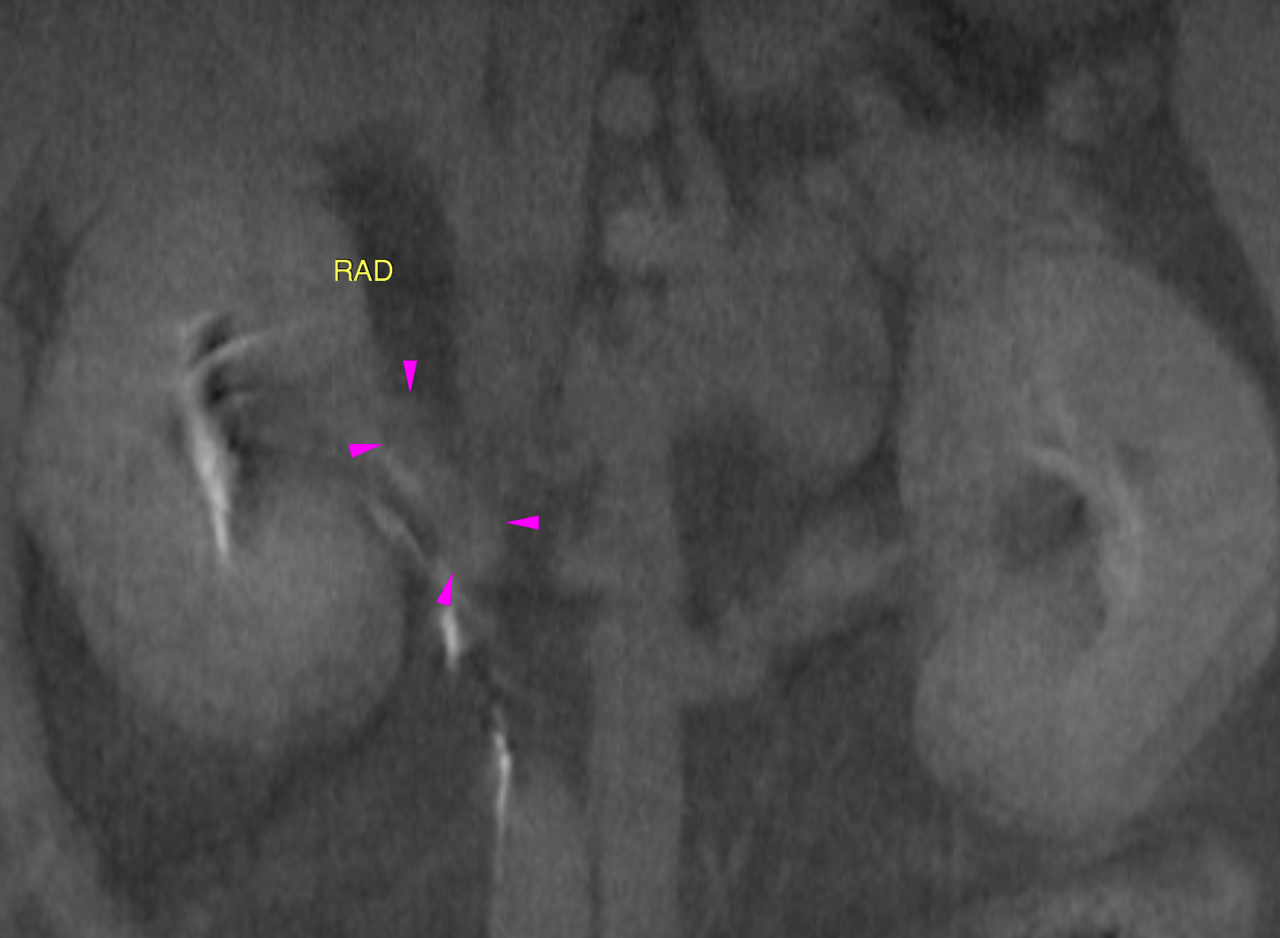

CT of the abdomen – A leftsided polygonal expansile and slightly ill defined adrenal mass of 4 x 3.5 x 4 cm is seen. The mass reveals extensive invasion into the caudal vena cava obstructing 60 % of the vascular diameter and expanding the vascular lumen signifcantly. The intravascular tumor extends at least 7 cm cranial from the right renal vein. Marginal blood flow is maintained. Pooling of contrast caudal to the vascular mass with differential contrast concentration is seen. The mass itself reveals a heterogenous attenuation pattern with non-uniform contrast enhancement. Mild localized retroperitoneal effusion and fat stranding is noted surrounding the mass.

¥ Leftsided adrenal mass with extensive vasular invasion meeting malignancy criteria ¥ Mild paraneoplastic retroperitoneal effusion ¥ Normal right adrenal gland Reactive mesenteric lymph node hyperplasia. The changes do not meet malignancy criteria at this point.